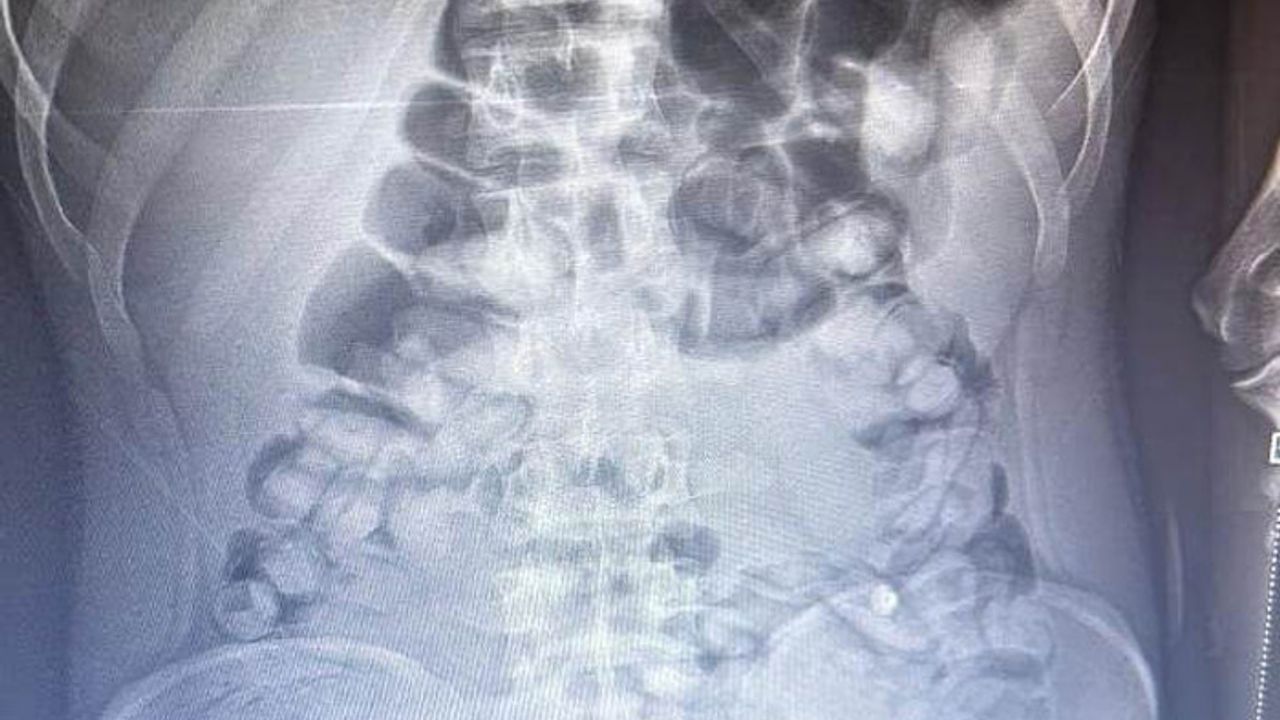

İl Emniyet Müdürlüğü Narkotik Suçlarla Mücadele Şube Müdürlüğü ekipleri, bir yolcu otobüsünde yaptığı denetimde, durumundan şüphelendiği yolcuyu hastaneye götürdü. Burada rdöntgeni çekilen yolcunun midesinde uyuşturucu tespit edildi. İlaç verilen yolcu, 1 kilo 134 gram Afyon sakızını doğal yollarla çıkardı.